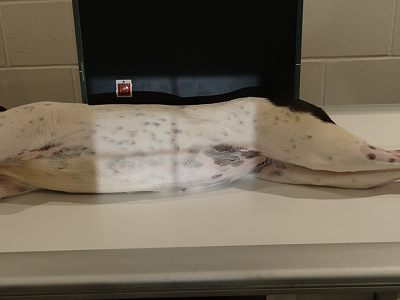

lateral projection of the abdomen

ventrodorsal projection of the abdomen

ventrodorsal projection of abdomen with the horizontal beam (lateral decubitus)

modified lateral projection